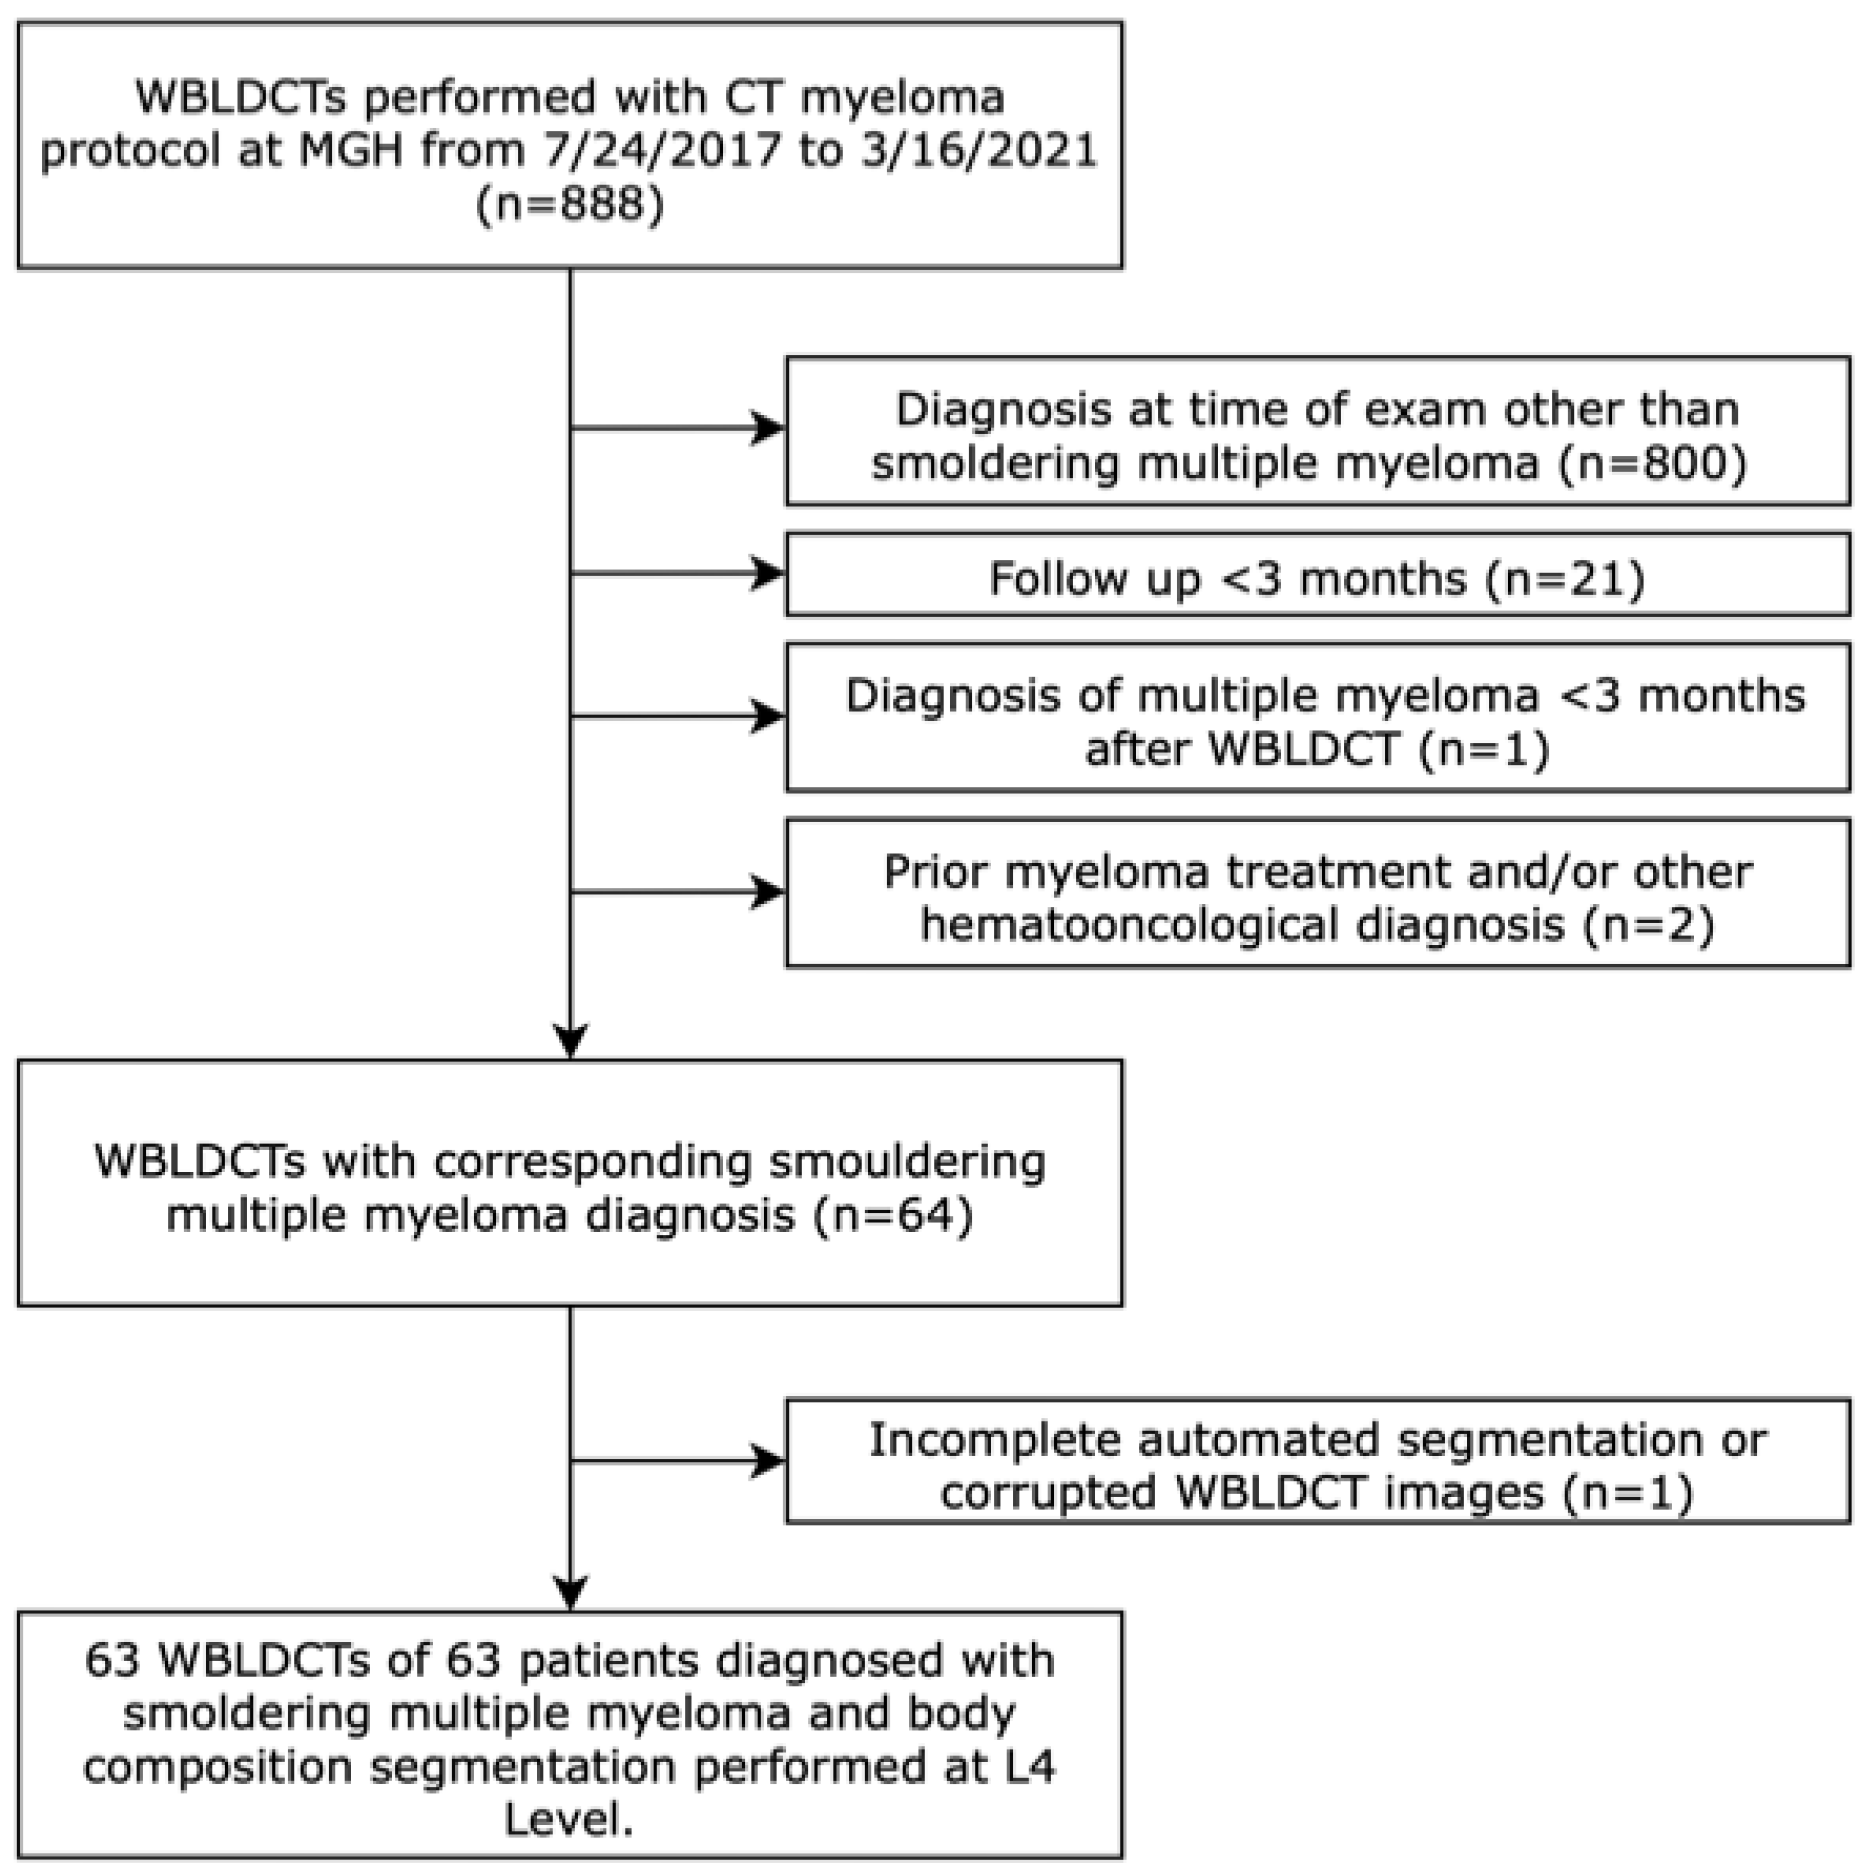

2.1. Study Cohort and Data Collection